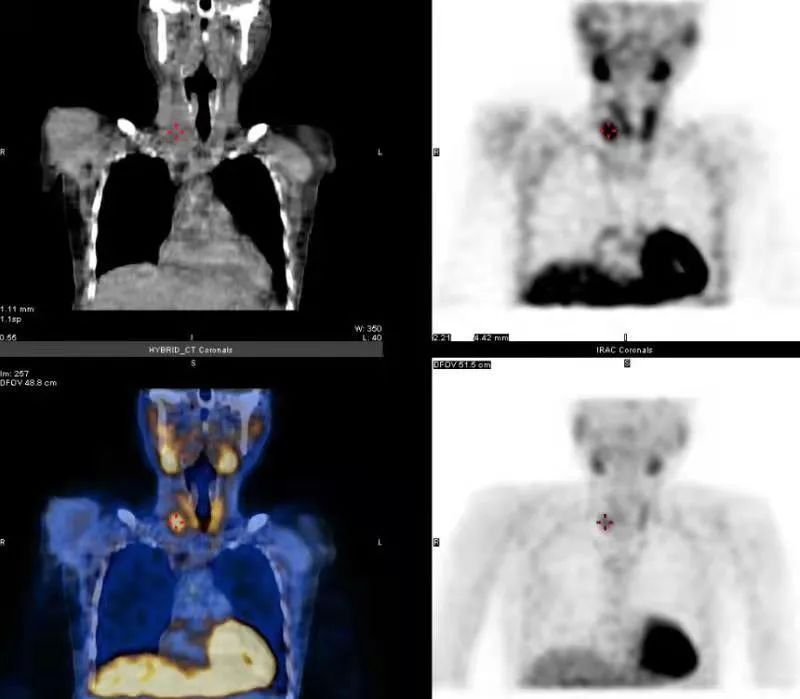

之后,赵先生进行了手术,原来认为的右侧“甲状腺肿物”,经切除及化验,确认为良性的甲状旁腺腺瘤,并且术中腺瘤切下即刻抽血,PTH已降至200ng/L左右。